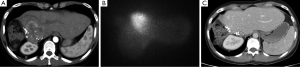

The radioembolization process is conducted in at least two parts. The first session, the mapping portion consists of a Technicium-99 macro-aggregated albumin SPECT scan during which particles mimicking the Yttrium-90 microspheres determine the percentage of lung shunting which may occur with the radioembolization procedure. If greater than 20% lung shunting occurs, then the patient is not eligible for radioembolization. Likewise, the Yttrium-90 dose may be modified based on the percentages of lung shunting. Also during this procedure, occlusion of the gastroduodenal artery or other collateral vessels may be performed to prevent retrograde flow of the microspheres, which can result in gastric and duodenal ulcers (15%). The radiation dose is calculated by the body surface area method or an empiric dose may be administered but is thought to carry higher rates of toxicity (49). The next procedure consists of the administration of the Yttrium-90 microspheres, which may be performed in a whole liver approach or sequential lobar treatments. The advantage of sequential treatments is to observe the effect of first radioembolization and to assure that sufficient contralateral liver reserve exists. Patients may be then monitored on an every 2-3 month basis after completion of therapy (Figure 4).

A 45-year-old woman with a diagnosis of diffuse liver metastases due to colon cancer requires a chemotherapy holiday due to neuropathy from therapy. She has been treated with FOLFOX and FOLFIRI. Given the diffuse nature of her liver metastases and clinical situation, Y90 radio-embolizaiton was recommended. Chemoembolization was considered to be an option but available results have shown better outcomes for smaller volume disease.